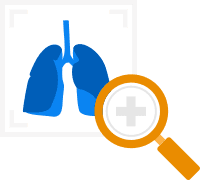

Computer-aided diagnosis

Reading X-ray images, CT, PET and MRI scans, ultrasound scans (including 3D and 4D), isotope scans, etc. Enhancing clinical images, measuring organ dimensions and blood flow, detecting pathological signs and suggesting a diagnosis.